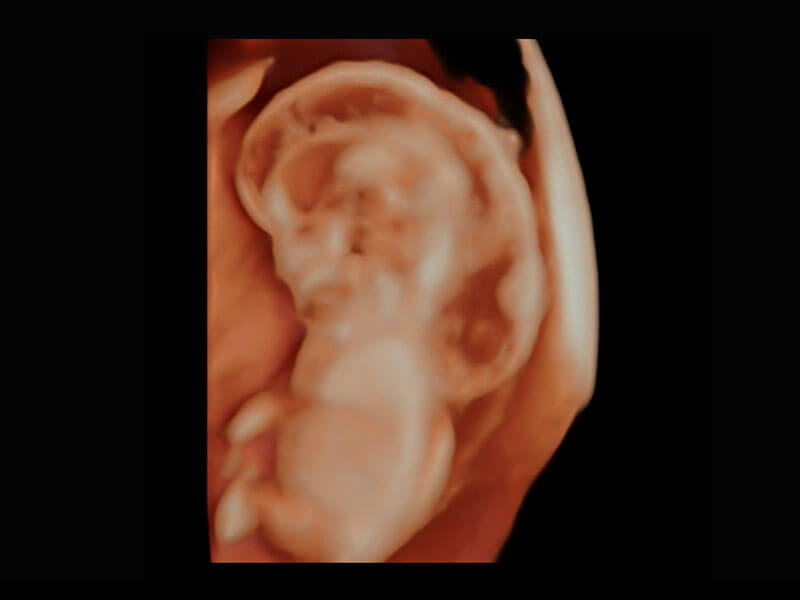

早孕筛查

P60在胎儿早孕期超声筛查中为您带来优异的图像质量。

• 早孕-胎心

• 高分辨率容积成像-早孕胎儿

• 胎儿体循环

• 光影成像-孕囊